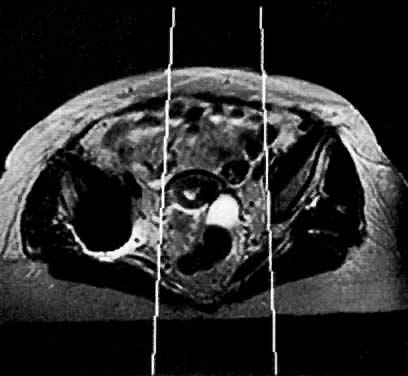

Fig. 57. Axial MRI shows the utility of MR in planning radiation ports. In this case, MR showed that the tumor extending into the right parametrium is not included in the radiation port.